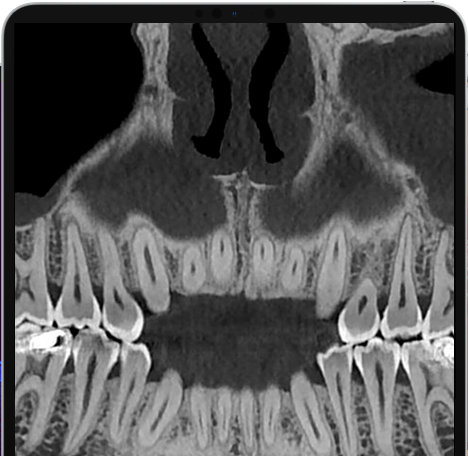

Veja exemplos de diagnósticos de imagem

- O gerador com ânodo giratório e ponto focal de 0,3 mm permite obter imagens de altíssima definição para ver detalhes e microestruturas que não podem ser investigados com dispositivos tecnológicos padrão;

- Algoritmos de reconstrução e processamento de imagem, resultado dos vinte anos de experiência da NewTom, permitem obter rapidamente imagens 2D e 3D excepcionais.

Com apenas algumas etapas simples, o NNT pode processar os dados adquiridos durante a varredura para criar uma vasta gama de imagens, que fornecem informações detalhadas sobre a anatomia do paciente. Posteriormente, eles podem ser salvos em um relatório ou distribuídos com a versão Viewer do software. O NNT também oferece diferentes modos de aplicação voltados especificamente para implantologia, endodontia, periodontia, cirurgia maxilofacial e radiologia.